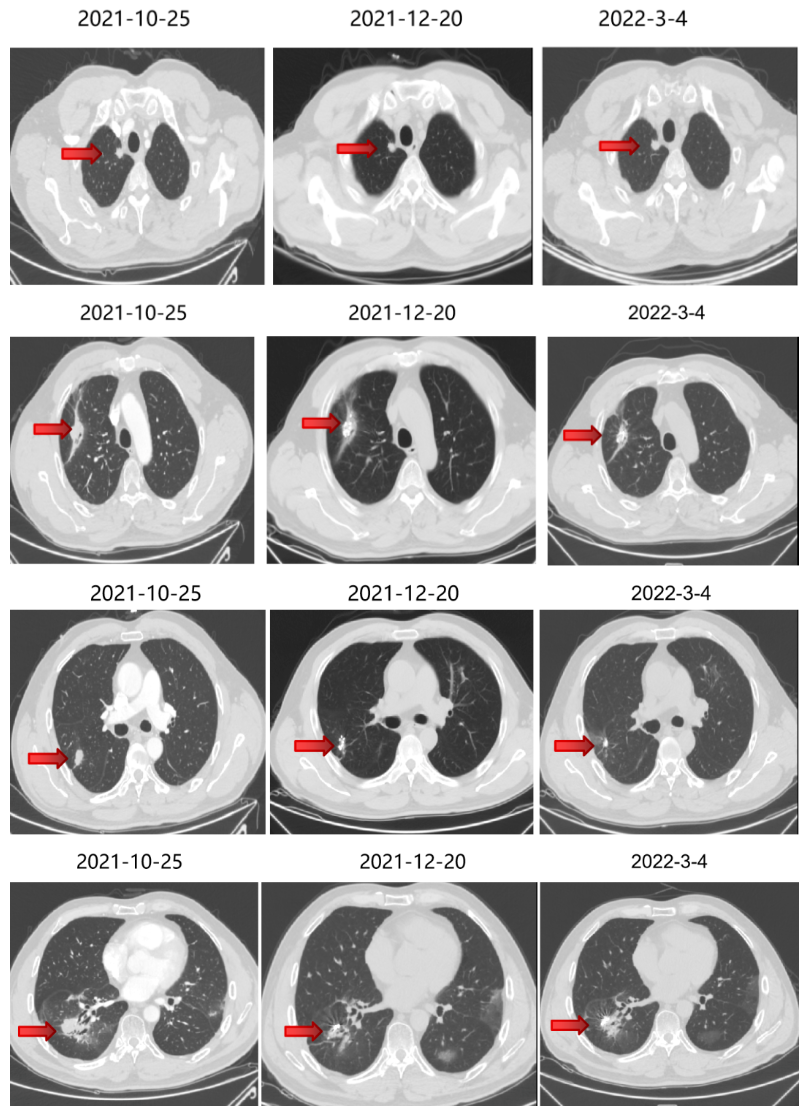

2021-10-29、2021-11-1 行CT引导下双肺转移灶放射性碘125粒子植入术。

继续曲氟尿苷替匹嘧啶片(TAS-102)40mg bid+瑞戈非尼40mg qd(2021-11始)至今。

五线治疗疗效:病灶控制良好。

局部治疗(四):粒子植入

2022-4-13、2022-4-15 行CT引导下双肺转移灶放射性碘125粒子植入术。

2022-4-21 肺转移组织基因检测。

4 目前状况

患者ECOG PS 1分,多程多线治疗耐受性良好,未出现高血压、蛋白尿、骨髓抑制等不良反应。

血常规、肝肾功能及肿瘤标志物无明显异常。

5 病程总结

PFS 1:15个月 ,PFS 2:12个月,PFS 3:5个月,PFS 4:5个月,PFS 5(目前):6.5个月,OS(目前):51.5个月。